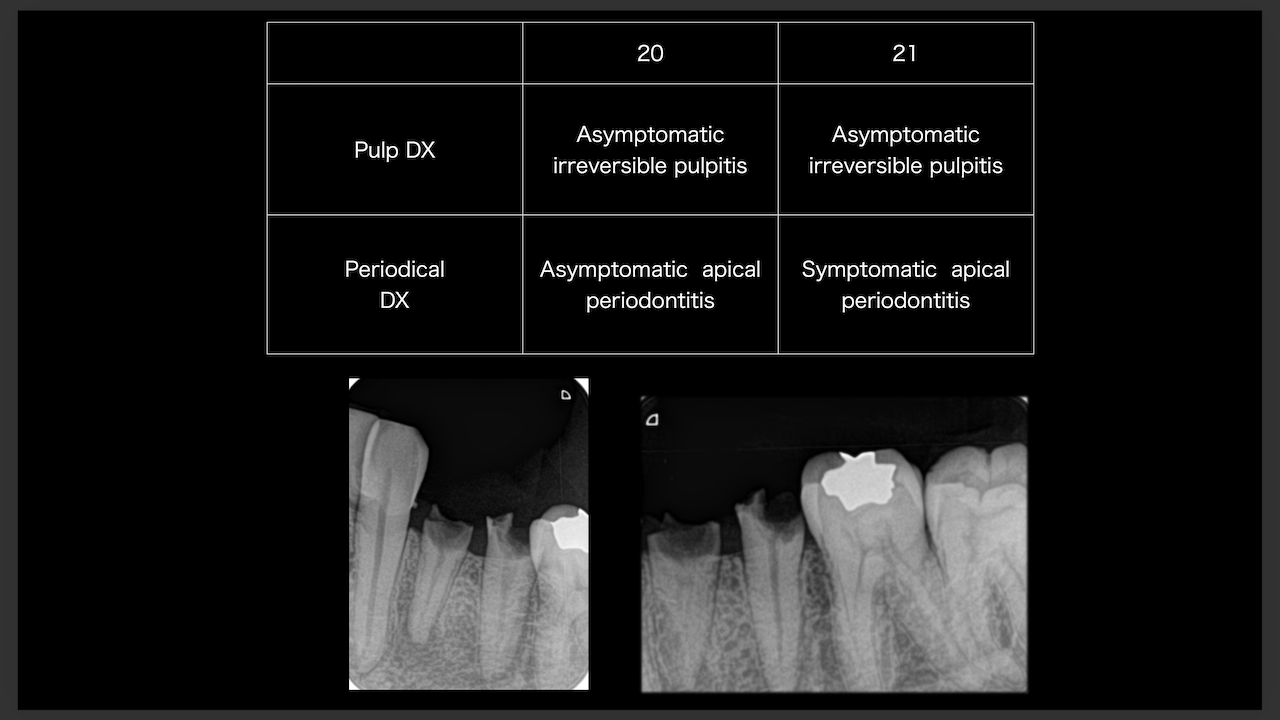

次は東京から参加のN先生。

術前/術後を比較した。

#29

#4

ラバーダム防湿をして行った根管治療の威力がわかったと思う。

素晴らしいケースだ。

次はN先生と同一法人のF先生。

#10のRCTと3M recallである。

#9,10と病変があるが、

#9はColdに2秒で反応し、その痛みが5秒でおさまったことから生活歯と判断し、

Cold, EPTに反応がなく打診痛もある#10を患歯と考え、#10のみ根管治療することとなった。

その際の成功率は86%である。

と術前に患者さんに告げて治療へ導入し以下のようになった。

3ヶ月しか経過していないが根尖病変は大きく減少した。

治療していない#9には変化があまりないがだからと言って手をつける必要性はない。

患者に症状がないからだ。

先生も診断の重要性を学ばれたと思います。

これからも頑張ってください。